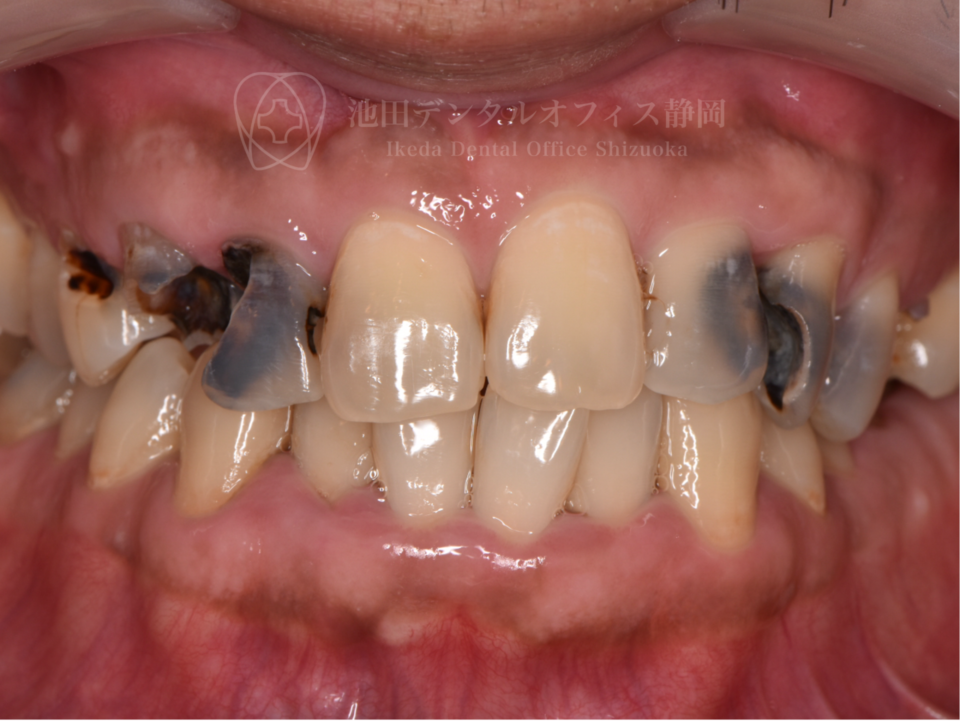

長年歯科へ通院できず、状態が悪化したため「歯医者に行くのも恥ずかしい」と悩んでいた患者さんです。歯の状態が悪く抜かなければいけない歯もありましたが、インプラント治療をしたくないとの希望があったため歯の移植などを行いできる限りご自身の歯を残しました。

歯科に対する恐怖心が強く、ご本人への負担が大きい治療は麻酔科の先生と連携して静脈内鎮静法で治療を行いました。移植後のセラミック治療により見た目と噛み合わせを改善しています。